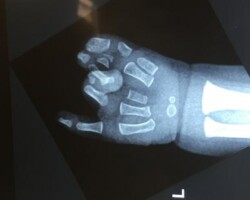

Διαχωρισμός σύνθετης πλήρους συνδακτυλίας

Παιδί με σύνθετη πλήρη συνδακτυλία του αντίχειρα, του δείκτη και του μέσου, στην οποία συμμετείχε μερικώς και ο παράμεσος. Αντιμετωπίστηκε με διαχωρισμό του αντίχειρα και απελευθέρωση της εγγύς φαλαγγοφαλαγγικής άρθρωσης του παράμεσου σε ηλικία 9 μηνών.